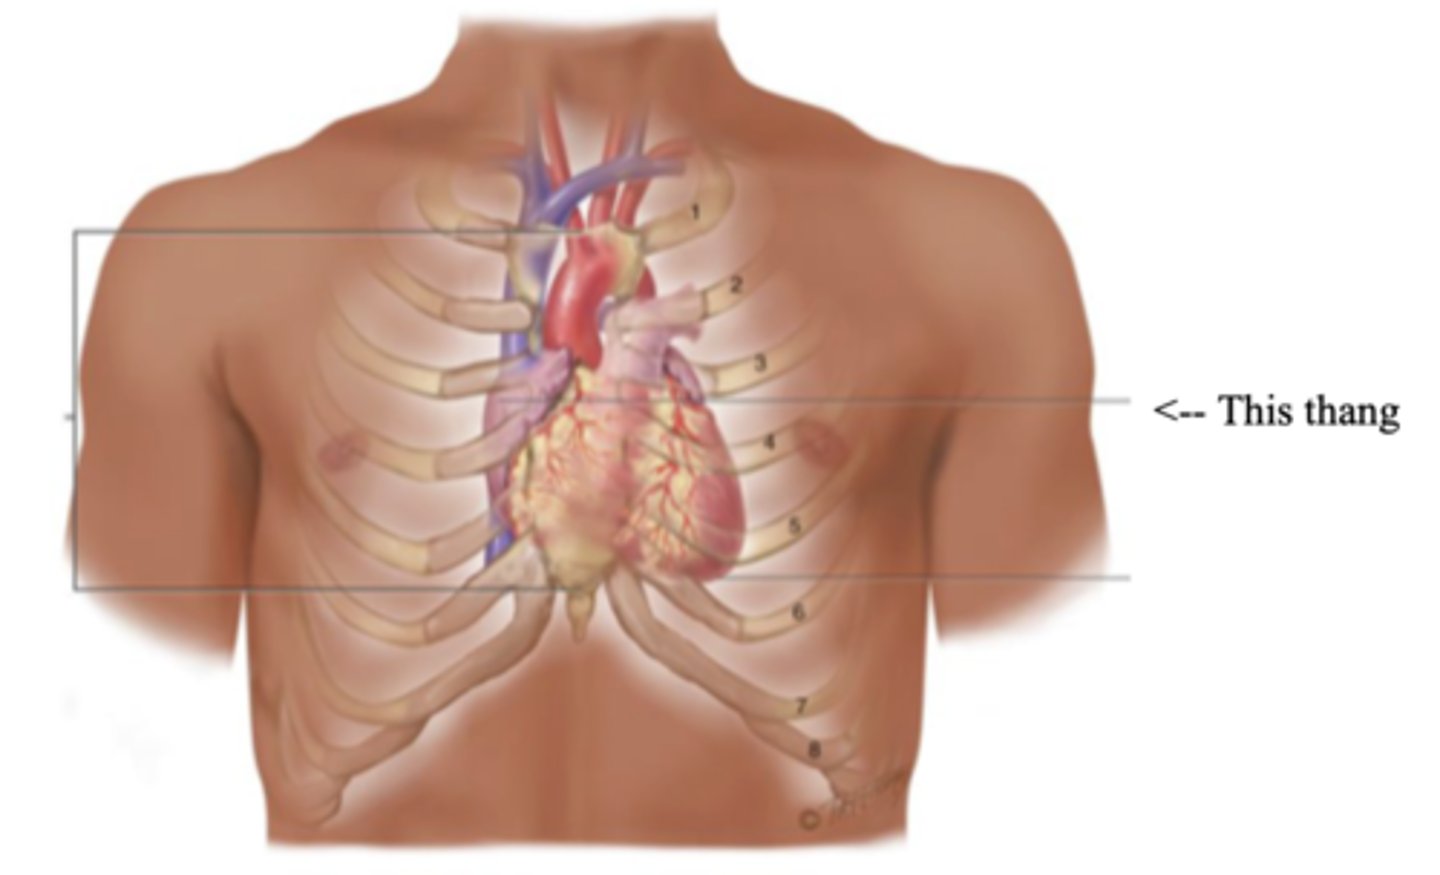

Precordium

The area on the anterior chest overlying the heart and great vessels

Mediastinum

The space located between the lungs where the heart is found

Apex (Heart)

The bottom part of the heart which points down to the left

Base (Heart)

The top broader part of the heart

Right Cardiac Border

An area formed by the right atrium

Left Cardiac Border

An area formed by the left ventricle

3 Layers of the Heart Wall

- Pericardium

- Myocardium

- Endocardium

Pericardium

Anatomy of the Heart

Myocardium

The muscular wall of the heart; does the pumping

Endocardium

The thin layer of endothelial tissue that lines the inner surface of the heart chambers and valves